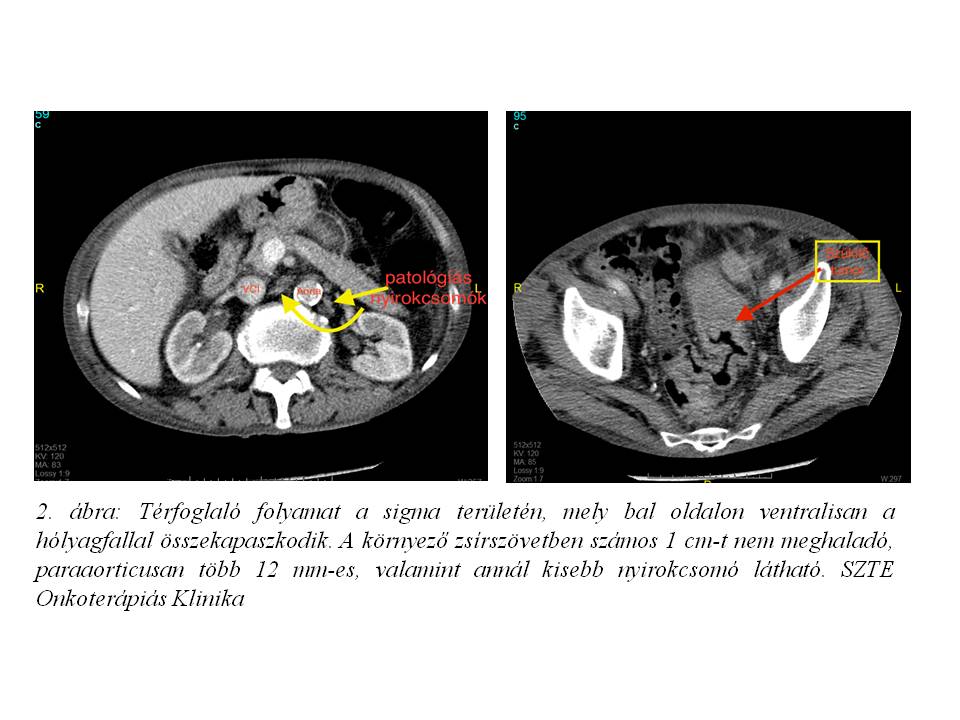

A szövettani mintavétel közepesen-jól differenciált adenocarcinomát igazolt. A képalkotó vizsgálatok alapján regionális, illetve PAO régióban detektálható lymphadenomegalia is igazolódott (1. ábra, 2. ábra).Stagingmellkas CT vizsgálat tüdőáttétet nem igazolt, tumor marker vizsgálatok minimális carcino-embrionalis antigén (CEA) emelkedést mutattak (4,74 M ng/ml, norm. tartomány‹4,70). Komplett kivizsgálás alapján a daganat iniciális stadiuma T4, N1 (LYM), M1 (PAO nyirokcsomó érintettség) lett definiálva, mely miatt, onkoteam döntés alapján, neoadjuváns kemoradioterápia indult 2014. júniusában (3. ábra, 4 ábra). A radioterápia indításától kezdve folyamatos compliance problémák nehezítették a kezelést. A beteg a szükséges kontrollvizsgálatokon nem vett részt, GI és vizeletürítési panaszaival SBO-n, sebészeti és urológiai ambulancián jelent meg, mely miatt sugárkezelését 11 frakció (19,8 Gy) leadását követően felfüggeszteni kényszerültünk. A beteg a sugárérzékenyítő, orális capecitabine (Coloxet, 825 mg/m2) citosztatikumot is csupán 1 hétig szedte. A fokozódó subileusos panaszok miatt urgens, székletpasszázst biztosító deviáló tranversostoma képzés történt SZTE Szebészeti Klinikán.